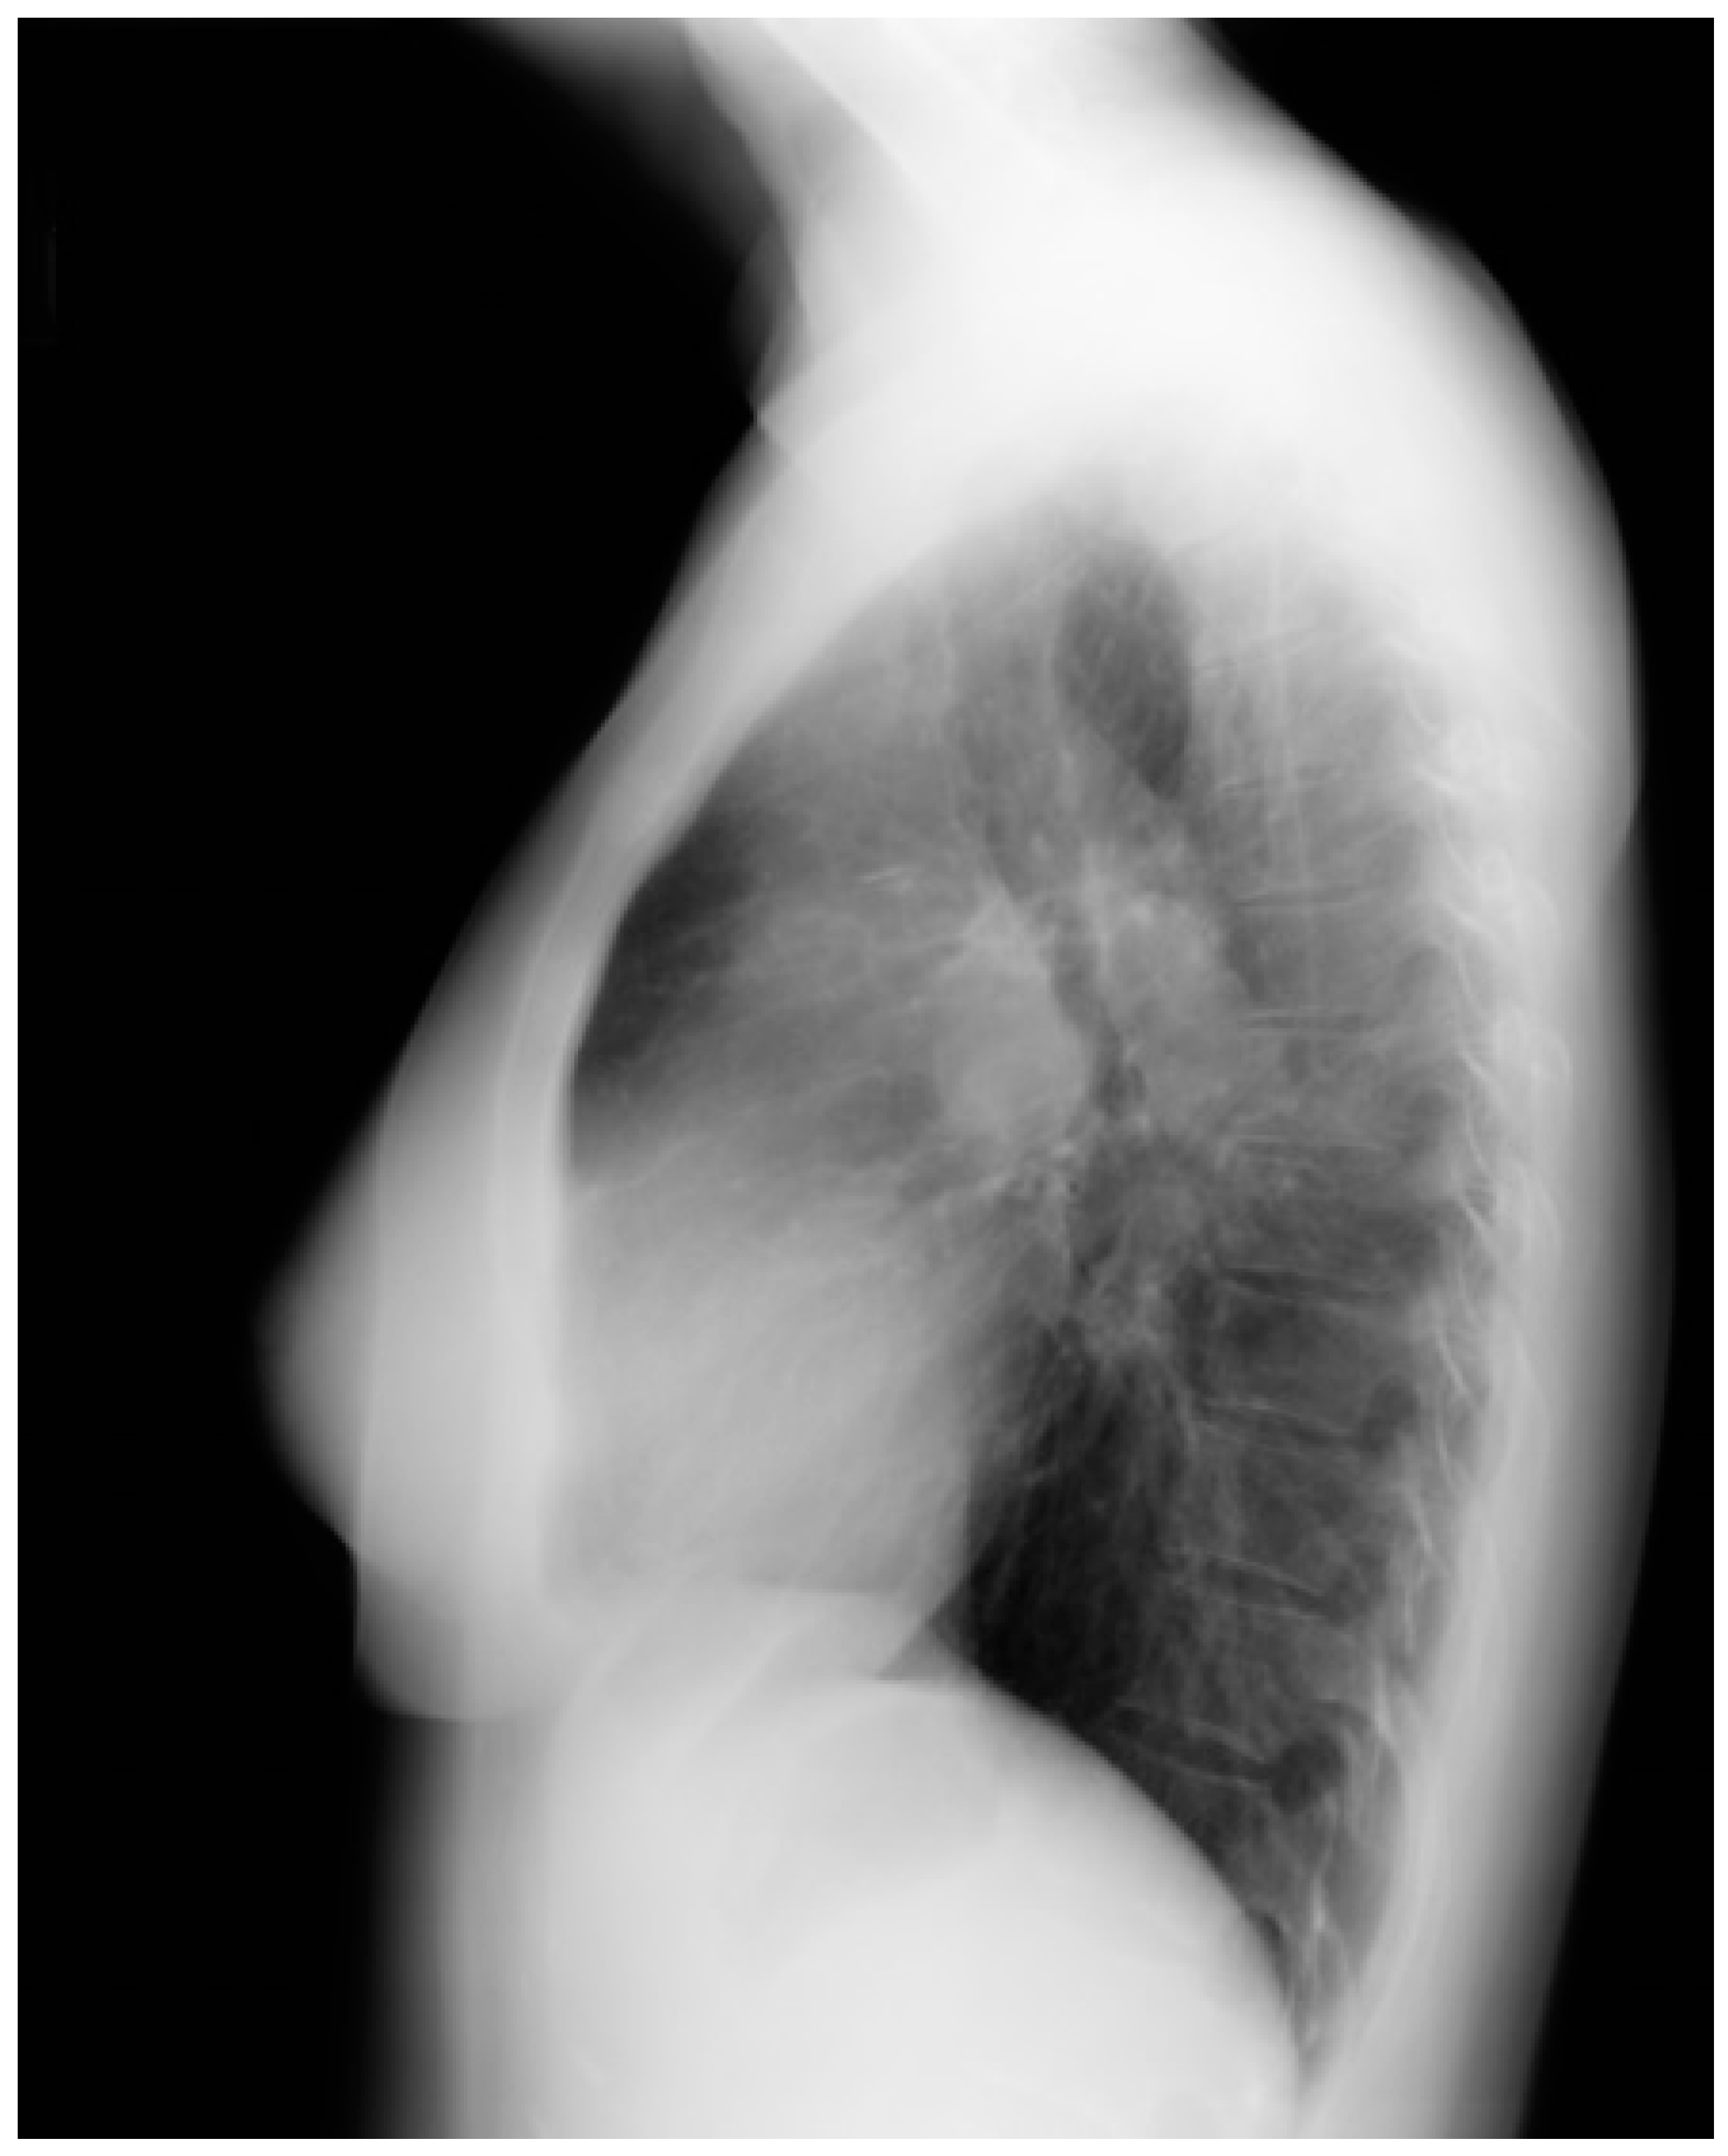

Lateral chest X-ray of Marfan syndrome: this chest X-ray was done on the same 24-year-old female above. It shows the dorsal kyphosis and pectus carinatum (also known as pigeon chest). The ascending, arch, and descending aorta were markedly dilated. Additional imaging measured the minimum thoracic aortic diameter to be 6 cm. She went on to have a mechanical aortic valve replacement, followed by aortic root and ascending aortic replacement via median sternotomy, and then descending aortic replacement via left lateral thoracotomy. A few years later she required an extensive abdominal aortic replacement with multiple arterial anastomoses to vital organs supplied by the abdominal aorta. She was followed for 30 years after her first diagnosis of MFS and her first aortic operation and remained NYHA functional class 1–2. Suspicion of the diagnosis of MFS in an asymptomatic patient that leads to a CXR is an important first step in the optimal care of MFS.